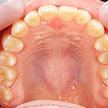

2. 術前上顎

上顎面観でやはり1,1番の翼状捻転および3,3番の捻転が著名。2次成長期を迎える患者様において、上顎歯列弓は劣成長と思われます。